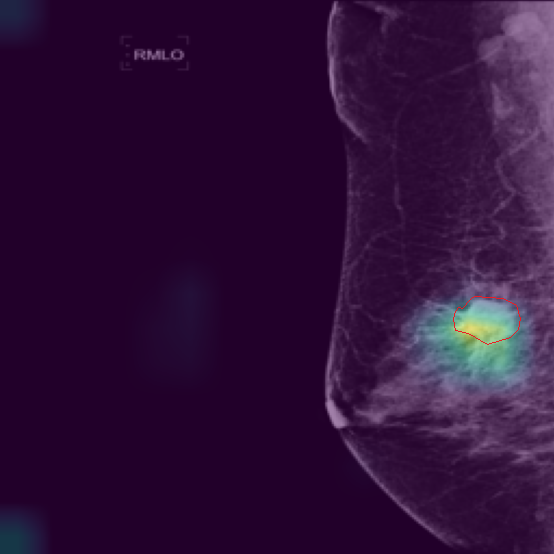

5.9 ViKL Provides Evidence for Clinical Decision

In our earlier sections, we discussed how ViKL enhances the image branch’s capability for detailed feature extraction by using text and manifestations that describe localized lumps. To directly observe this enhanced feature extraction ability, we utilize the class activation map (CAM) [62], a common tool for visualizing neural network activations. Specifically, we employ Grad-CAM [63] to generate activation maps from the third layer of the ResNet50 model, which has been fine-tuned using ViKL on the MKVL dataset. Additionally, for accurate visualization and comparison, we include markings of lumps as annotated by professional radiologists. The results of this visualization are showcased in Fig. 6. These visualizations demonstrate ViKL’s effective localization of small lesions, highlighting its refined ability to capture minute features in medical imaging.